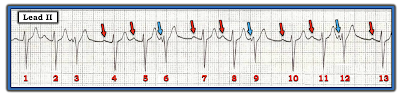

The rhythm strips in Figure-1 were obtained from 2 different patients. Both patients were hemodynamically stable at the time these rhythm strips were recorded.

The underlying rhythm in Tracing A is sinus — as determined by the presence of upright P waves with fixed PR interval preceding beats #1,2; 4,5; 7,8; 10,11; and 13, in this lead II monitoring lead. The QRS complex of sinus beats is narrow.

- Every-third-beat occurs earlier-than-expected and looks slightly different. That is — the QRS complex of beats #3, 6, 9 and 12 each have a smaller r wave, and a less deep S wave than do sinus beats. The QRS complex for each of these early beats looks to be narrow and preceded by a premature P wave (BLUE arrows in Figure-2 — compared to the RED arrows that highlight sinus P waves).

| Figure-2: To Figure-1 — I’ve added RED arrows that show sinus-conducting P waves — and BLUE arrows over what looks to be PACs occurring every-third-beat (See text). |